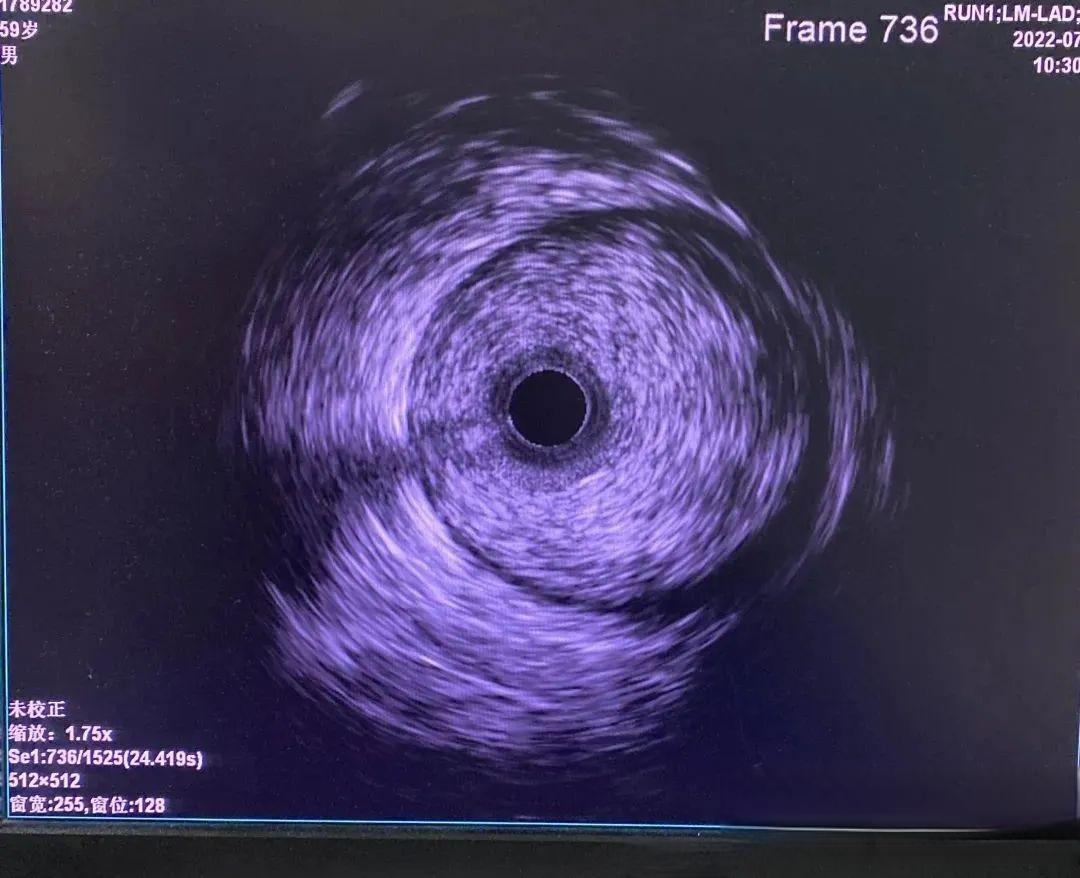

在医学影像领域,一项突破性的技术正在悄然改变心血管疾病的诊断和治疗方式。这就是血管内超声(Intravascular Ultrasound,简称IVUS)技术,它不仅让医生能够“亲眼”看到血管内部的情况,还为精准医疗开辟了新的道路。

IVUS技术的核心原理是通过导管将微型超声探头送入血管内部,实时显示血管的截面图像。这种技术能够提供分辨率约为100微米,成像深度约为7毫米的血管横截面结构图像,清晰显示血管壁的三层结构:内膜、中膜和外膜。更重要的是,IVUS能够辨认钙化、纤维化和脂质池等病变,发现冠脉造影无法显示的血管早期病变。

在心血管疾病诊断中,IVUS的应用可谓如虎添翼。以冠状动脉疾病为例,IVUS能够精确测定管腔、血管直径,判断病变严重程度及性质。它不仅能清晰显示血管壁厚度、管腔面积和形状,还能评估斑块性质和特点,为医生制定更加个体化的诊疗方案提供重要依据。例如,在评估冠状动脉狭窄程度时,IVUS可以提供比冠脉造影更准确的数据,帮助医生判断是否需要进行介入治疗。